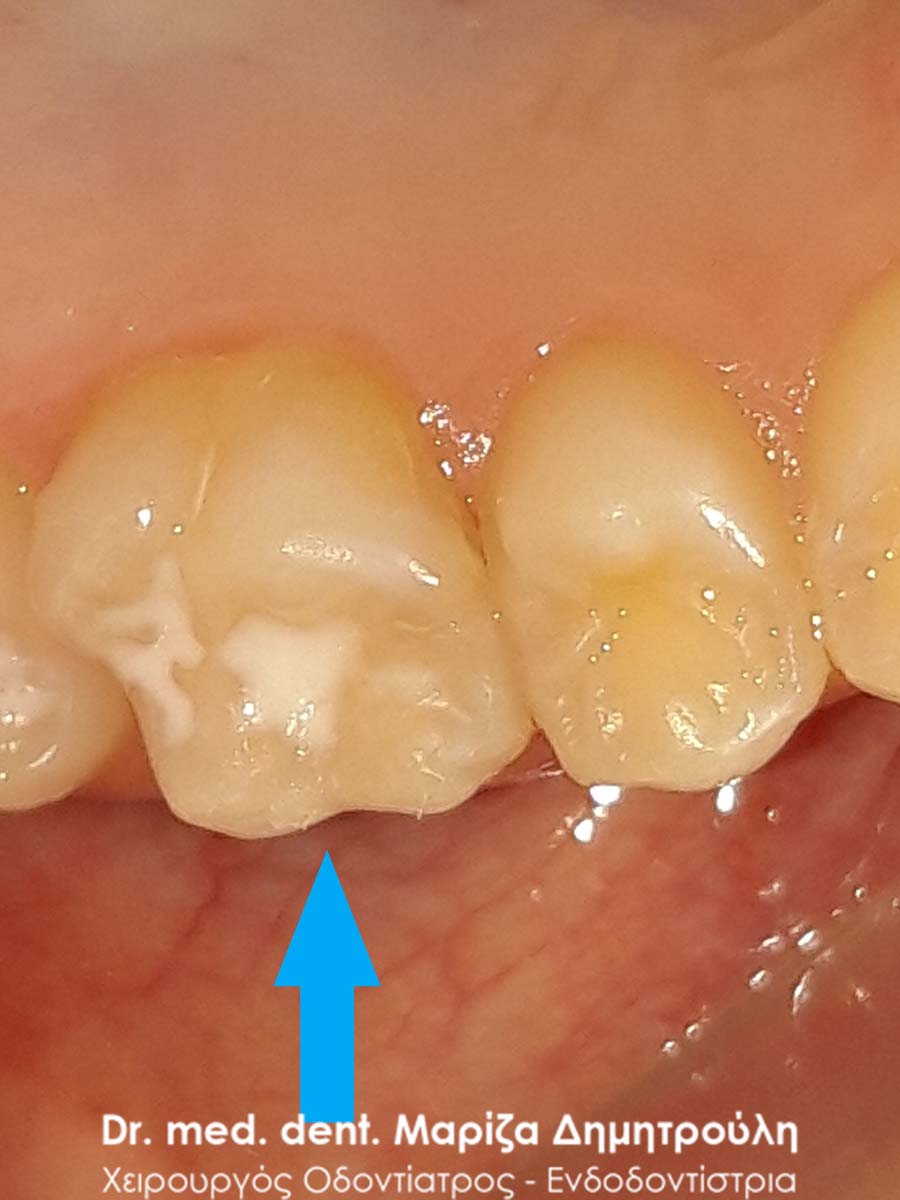

Στο αγόρι αυτό τοποθετήθηκε προληπτική κάλυψη στη μασητική επιφάνεια του μόνιμου κάτω πρώτου γομφίου, ώστε το δόντι να είναι προστατευμένο από την τερηδόνα. Η κάλυψη της μασητικής επιφάνειας ενός δοντιού με sealant μειώνει την κατακράτηση υπολειμμάτων τροφών στις σχισμές και τις αύλακες του δοντιού αυτού με αποτέλεσμα να συγκεντρώνονται και λιγότερα μικρόβια στο δόντι. Παράλληλα το παιδί μπορεί να βουρτσίζει πιο αποτελεσματικά και εύκολα τα πίσω δόντια καθώς μειώνονται οι πτυχές του δοντιού, όπου παγιδεύονται συνήθως τροφές.

Ο χρόνος ζωής ενός sealant κυμαίνεται από 2 – 5 χρόνια.

ΜΕΤΑ